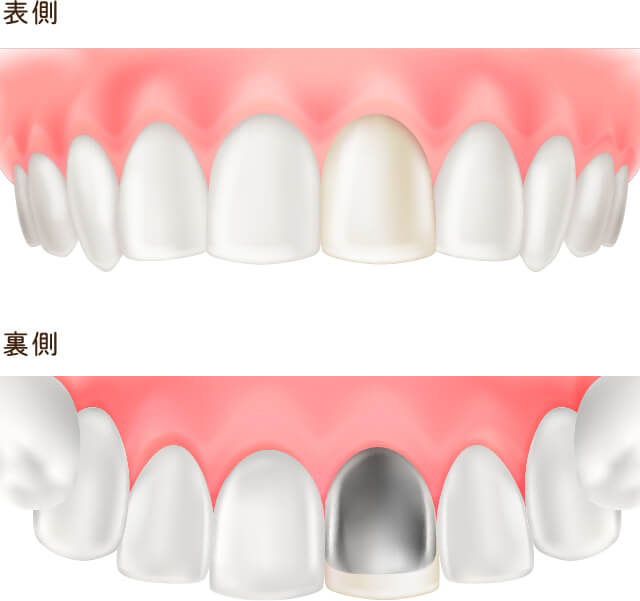

レジン前装冠(前歯被せ物)

前歯に対しての被せ物治療。コンポジットレジンでは対応できない大きなむし歯や根管治療終了後のケースに使用される。

裏面は金属で強度を保ち、表面は白いレジンで覆われているが、レジンに汚れや着色が付着しやすくむし歯の再発や審美的に優れなくなる可能性がある。